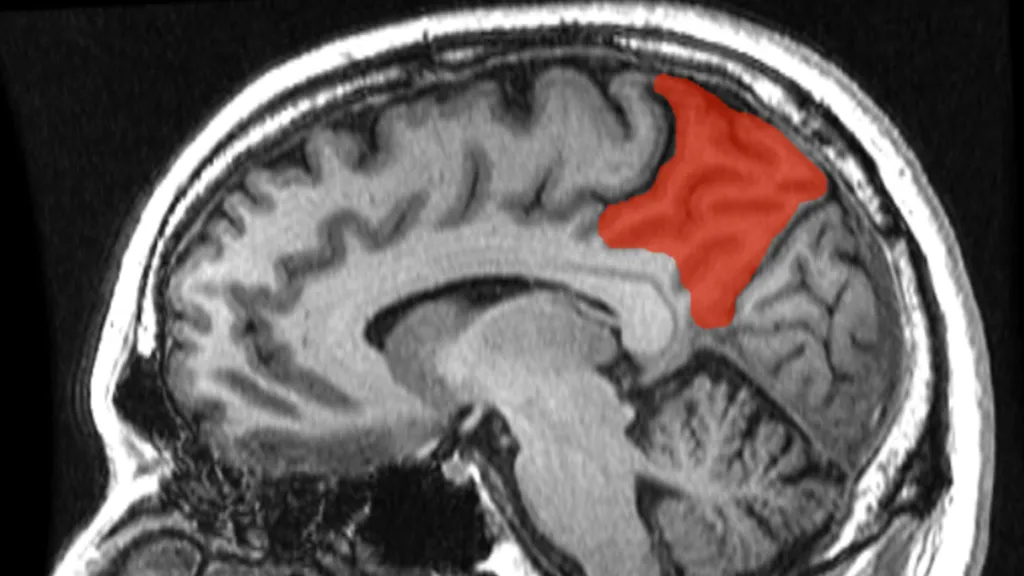

Vědci pomocí umělé inteligence dokázali identifikovat, které sítě se aktivovaly při různých příležitostech. Zajímala je mozková kůra, svrchní vrstva mozku, která se podílí na mnoha vyšších funkcích lidského mozku, včetně paměti, učení, uvažování, řešení problémů a emocí. Zkoumali také, jak aktivita v těchto různých sítích souvisí s tím, co se v jednotlivých scénách nachází, včetně lidí, zvířat, předmětů, hudby, řeči a vyprávění.

Zjistili, že 24 různých mozkových sítí je spojeno s konkrétními aspekty smyslového nebo kognitivního zpracování informací, například rozpoznávání lidských tváří nebo těl, pohybu, míst a orientačních bodů, sociálních interakcí a neživých objektů a řeči. Skeny také ukázaly vztah mezi oblastmi mozku, které lidem umožňují plánovat, řešit problémy a určovat priority informací.